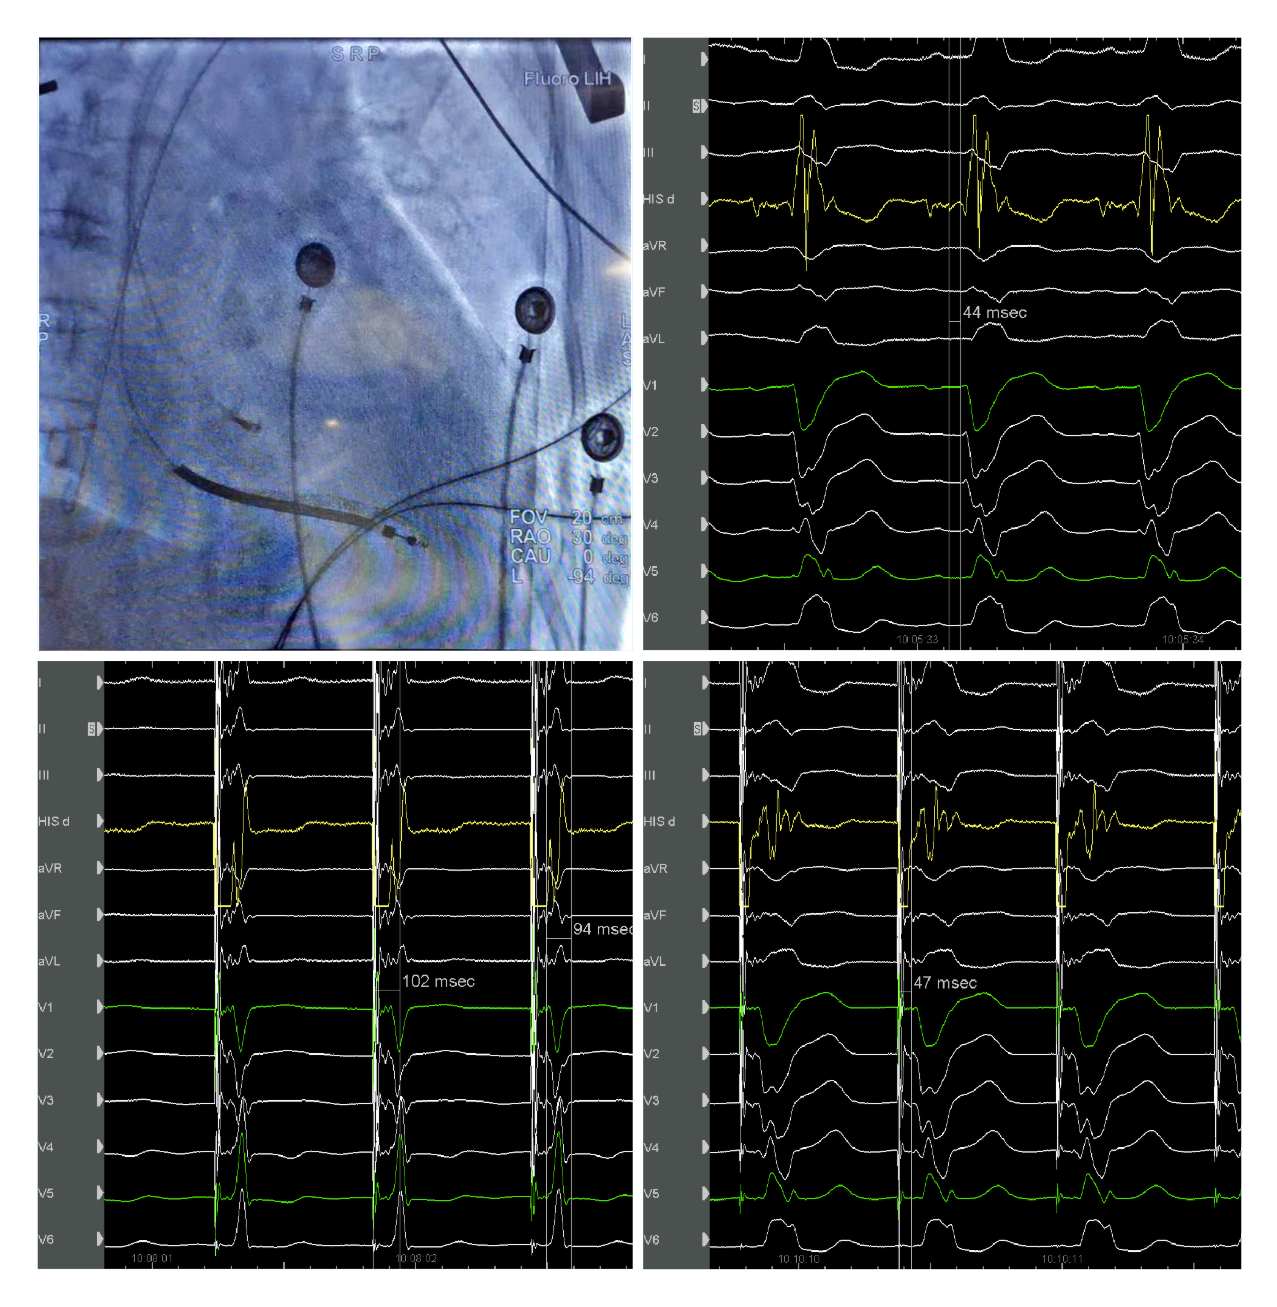

华体会体育官方网站 起搏团队演示了一例左束支起搏纠正完全性左束支阻滞用于治疗经典CRT适应症的病例。该患者为女性, 69岁,诊断:扩张型心肌病,完全性左束支传导阻滞,心功能III级,心电图显示经典完全性左束支阻滞图形,QRS193ms,心超LVD 73mm,EF 30%,符合CRTD适应症。术中顺利穿刺左侧腋静脉,在C315鞘管导引下3830电极标记到HIS电位,高电压起搏可纠正左束支阻滞,但纠正阈值较高8V/1.5ms。

(上图左上为希氏束的影像位置;右上为希氏束电位图;右下为低电压选择性希氏束起搏波型与自身一致;左下为高电压8V/1.5ms希氏束起搏纠正完左)

随后3830导线往心尖方向前移1cm拧入,同时监测起搏图形及单极阻抗,到位后起搏心电图显示不完全性右束支阻滞图形,左束支阻滞消失,测量V5导联左室达峰时间84ms,单双极高低电压起搏一致,提示夺获了左束支,夺获阈值0.7V/0.5ms。

(上图中左上为单极高电压起搏,右上为单极低电压起搏,左下为双极高电压起搏,右下为双极低电压起搏)

之后顺利植入心房导线及除颤导线,连接CRTD,调整AV间期融合右束支下传后得到完全正常化的QRS图形,起搏QRS时限97ms。